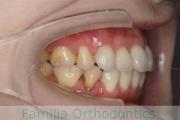

No.22V-169

- 主な症状:

- 上顎前突

- 年齢:

- 14歳

- 性別:

- 女性

- 抜歯部位

- 上:

- 44

- 下:

- |1

- 主な使用装置:

- FEA 022

- 治療にかかった費用:

- 88万円

上の前歯が出ているのを治したいということで来院されました。上下のあごのズレが強く、上は小臼歯を、下は前歯を一本抜歯で対応しました。約2年半、30回程度の通院をしていただきました。前歯の移動量が大きく、歯根吸収のリスクが高いケースでした。